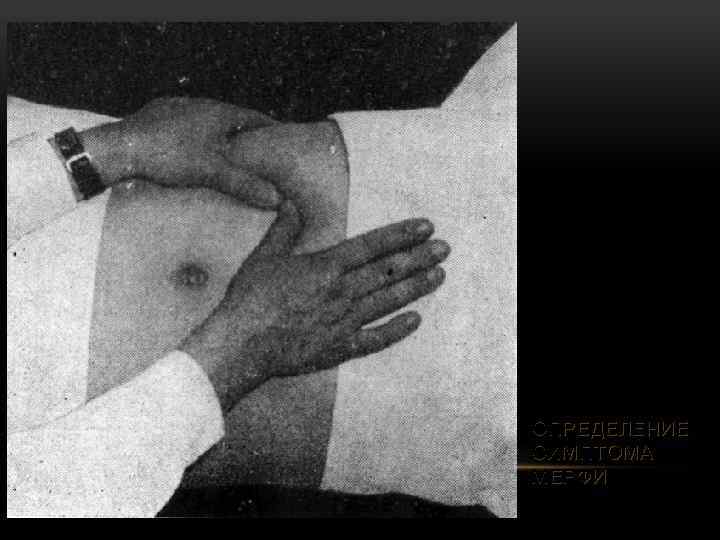

ОПРЕДЕЛЕНИЕ СИМПТОМА МЕРФИ

ОПРЕДЕЛЕНИЕ СИМПТОМА МЕРФИ